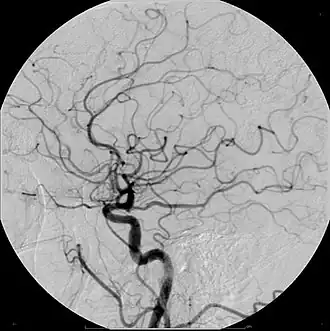

Un medio de contraste es cualquier sustancia que se usa para mejorar la visibilidad de estructuras o fluidos dentro del cuerpo. Un ejemplo de esto son los líquidos opacos a la radiación que se utilizan durante un diagnóstico de rayos X, para resaltar las características que hay de un tejido a otro.[1]

Se administran por las vías en que mejor se distribuyen por la estructura a ser examinada, ya sean ingeridos o por enema en el caso del tracto digestivo, inhalados para las vías respiratorias o inyectados para visualizar los vasos sanguíneos, órganos y tejidos.